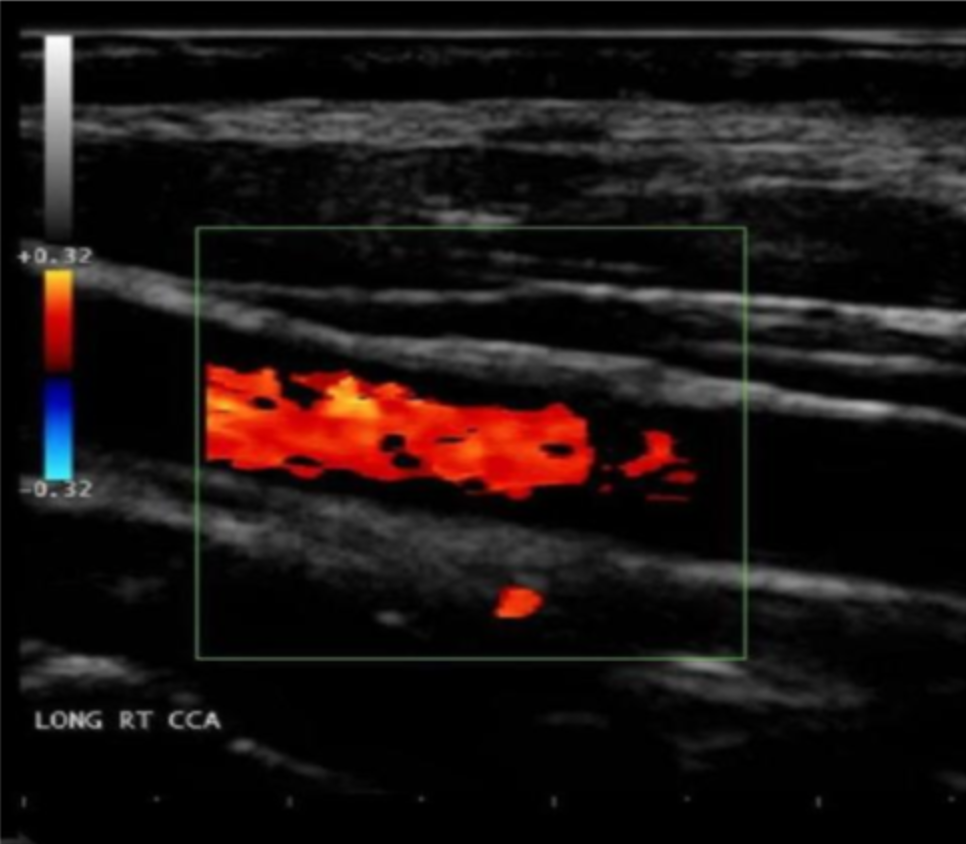

Which of the following machine settings will improve the attached image?

a. activate electronic focusing

b. activate electronic steering

c. decrease sample volume size

d. decrease color persistence

activate electronic steering